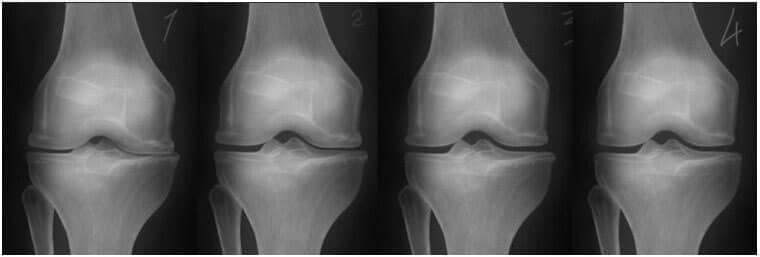

1. Az ízület elégtelen táplálkozása. A

porcszövet megsemmisül.

2. Az ízület porcszövetének

regenerálódása 2 héttel a "Steplex" alkalmazásának megkezdése

után.

3. Az ízület porcszövetének regenerálása 3 héttel

a "Steplex" használatának megkezdése

4.Egészséges ízület a "Steplex" használatának

befejezése után.

- Az alábbi röntgenfelvétel a térdízületek regenerálódásának tipikus mintázatát mutatja.